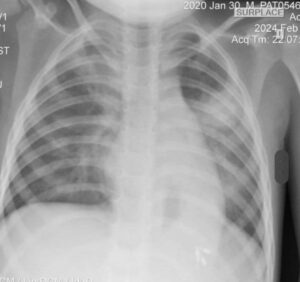

មុនមកដល់មន្ទីរពេទ្យគន្ធបុប្ផាភ្នំពេញ, កុមារដែលមានជំងឺរលាកសួត និងដំបៅក្រពះរូបនេះ បានបាត់បង់ឈាមរហូតដល់ ៦០%ទៅហើយដោយអាការៈក្អួត និង ហូរឈាមតាមទ្វារបាត។

បន្ទាប់ពីថែទាំ និងព្យាបាលរយៈពេល២៣ថ្ងៃ យ៉ាងយកចិត្តទុកដាក់ដោយក្រុមគ្រូពេទ្យជំនាញនៃមន្ទីរពេទ្យគន្ធបុប្ផាភ្នំពេញ រួចមក, បច្ចុប្បន្នកុមាររូបនេះបានជាសះស្បើយ និងត្រលប់ទៅផ្ទះវិញជាមួយស្នាមញញឹមយ៉ាងរីករាយ។ មូលនិធិគន្ធបុប្ផាកម្ពុជា សូមថ្លែងអំណរគុណចំពោះសប្បុរសជនទាំងអស់ដែលតែងតែបរិច្ចាគថវិកា ដើម្បីរួមគ្នាសង្រ្គោះជីវិតទារក កុមារ ដែលជាអនាគតដ៏ភ្លឺស្វាងរបស់កម្ពុជា។